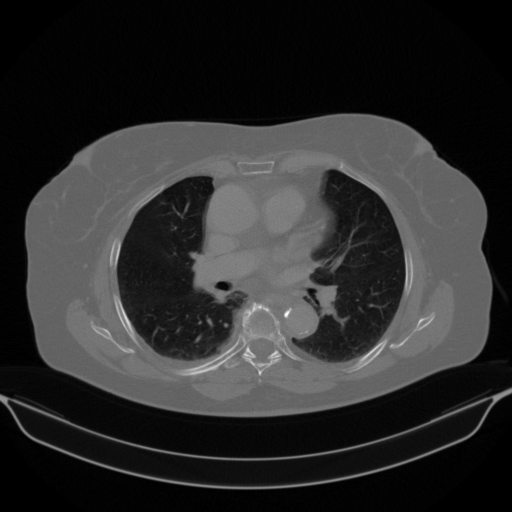

Original VENOUS CT scan

Lung window (WL -600, WW 1500 β†’ Low βˆ’1350, High +150)

Actual HU range: [-1024.0, 150.0]